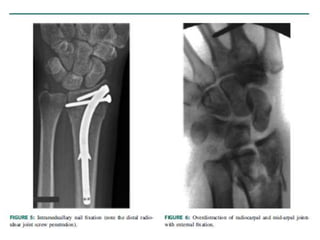

Tutores externos

• Fragmentos son pequeños y cercanos a la articulación,

• Gran conminución

• Fractura expuesta

• Se puede utilizar clavos percutáneos y emplearlos por un lapso de 4 a

6 semanas

TECNICA DE TUTOR MAS AUMENTO CON

CLAVOS

Distal Radius Fractures: Approaches, Indications, and Techniques. Current concept. Ram K. Alluri. 2016 by the American Society for Surgery of the Hand.